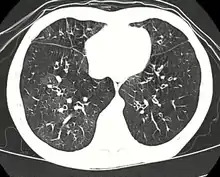

High resolution CT scan showing bronchiolitis obliterans with mosaic attenuation, bronchiectasis, air trapping and bronchial thickening[3]

Medical imaging

Early in the disease chest radiography is typically normal but may show hyperinflation.[6] As the disease progresses a reticular pattern with thickening of airway walls may be present.[4][6] HRCT can also show air trapping when the person being scanned breathes out completely; it can also show thickening in the airway and haziness in the lungs.[11] A common finding on HRCT is patchy areas of decreased lung density, signifying reduced vascular caliber and air trapping. This pattern is often described as a "mosaic pattern", and may indicate bronchiolitis obliterans.[6]